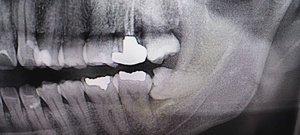

歯の詰め物(金属・銀歯)や薬剤の影響

古い銀歯や金属製クラウンから金属イオンが溶出し、口腔粘膜との接触でアレルギー反応が生じる場合があります。クロム・ニッケル・金・水銀などが原因物質となることがあり、金属アレルギーのある人は特に注意が必要です。

組織検査(生検)が必要なケースとは?

白斑が厚く、患部が硬い、出血しやすい

痛みが強く、潰瘍がある

がん化のリスクを排除したい場合

このような場合には粘膜の一部を採取する生体検査(生検)が行われます。